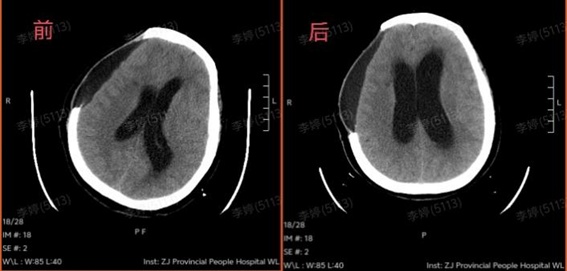

康复团队为王阿姨制定了个性化促醒及并发症预防康复治疗方案,全家人也在积极配合,经过治疗,王阿姨睁眼了,但眼神呆呆的,叫也没反应,手脚也不怎么动,好像整个人被“定”住了。头颅CT复查发现脑积水加重,脑脊液排不出,压住大脑,影响康复效果。

第一步:先“通水管”。神经外科为王阿姨做了颅骨修补和脑积水引流手术,把“堵住”的问题解决了。